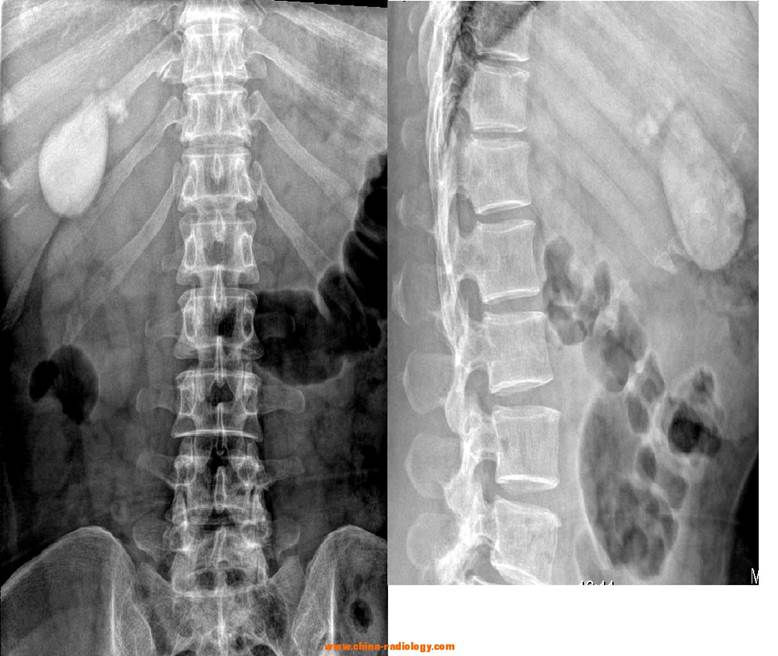

下图,男性,46岁,反复右上腹痛20余年加重10天,为持续性钝痛,不向它处放射,无恶心及呕吐;无发热及黄疸。对症治疗缓解。以后右上腹痛反复发作,与进食无明显关系。每2~3年发作1次。

胆囊钙乳多因胆囊颈部有结石梗阻,胆汁长期滞留,内含蛋白和碳酸钙样物质,胆囊壁有钙质沉着,使胆汁变为“白胆汁”,本例胆囊颈部结石影显示不清,因胆囊呈高密度影为主混杂密度影,倒是符合“胆囊钙乳症”的表现。